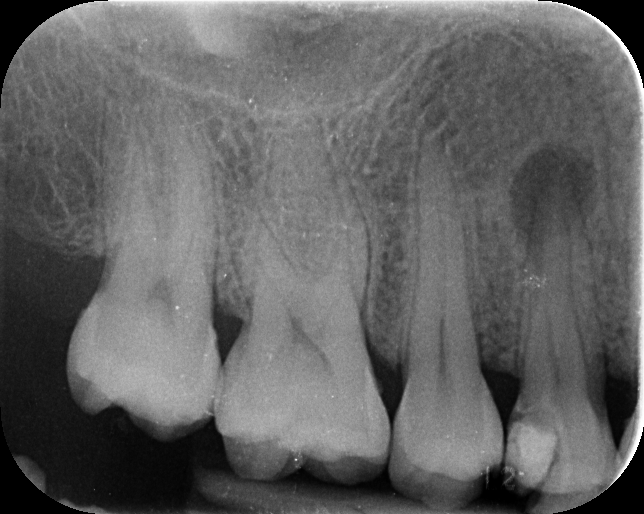

Upon examination and radiographic analysis, I found that the previous dentist had not properly diagnosed the underlying problem. The tooth was nearly lost due to the infection. The patient was very concerned and expressed a strong desire to save the tooth at any cost. I explained that the prognosis was poor, but I would use my best skills to try to save it.

- I recommended root canal therapy. While I usually complete this in a single visit, in this case, I planned a two-visit approach due to the severity of the infection.

- In the first visit, I placed an intracanal medicament (calcium hydroxide) to help heal the lesion.